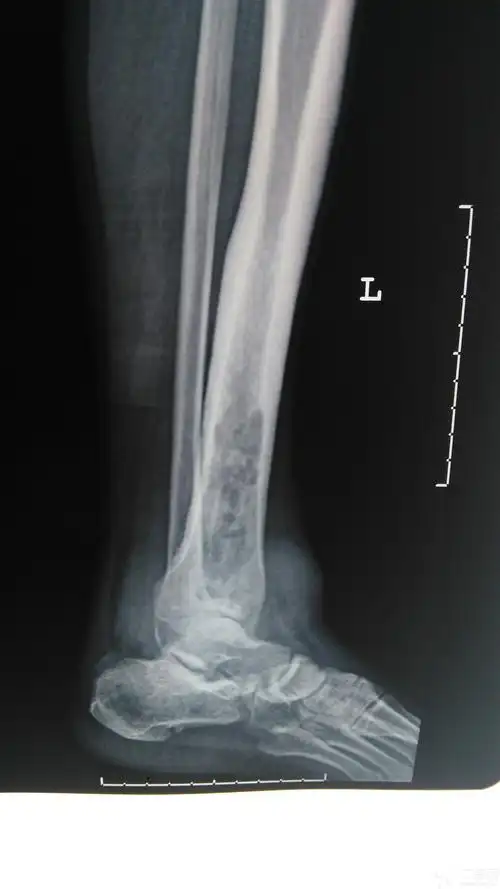

左胫骨慢性骨髓炎